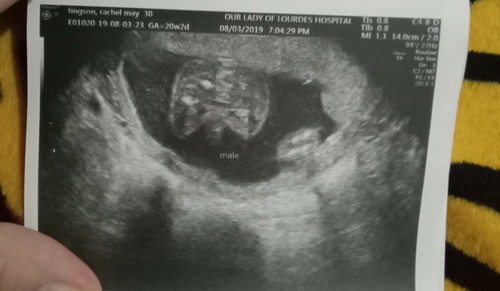

it's BABY BOY

Mommy 4.28 CM CLOSE CERVIX. Hmmm bed rest ako